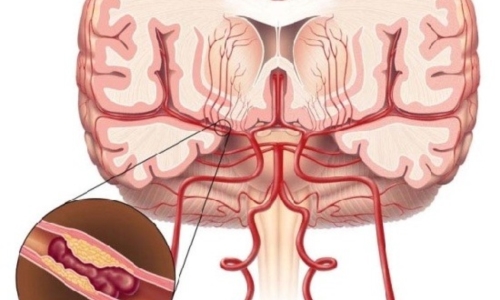

건강보험심사평가원 자료에 따르면 뇌출혈로 병원을 찾은 환자보다 뇌경색으로 내원한 환자가 5배 이상 많았다고 하는데요 뇌경색은 뇌로 통하는 혈관이 막히면서 뇌 조직이 점차 괴사하게 되는 질환으로 날씨가 추워지는 겨울철에 특히 발생 가능성이 높은데요 혈관이 수축 하게 되면서 혈압 상승으로 이어지면서 뇌혈관 질환이 발생하게 되기 때문입니다.

뇌경색 원인은 동맥경화증으로 시작합니다. 병이 든 혈관 어떤 곳에든 핏덩어리가 생겨나면 심장에서 뇌로 흐르는 혈액의 흐름을 방해하게 됩니다. 만약 핏덩어리가 내경동맥이나 뇌혈관을 막게 되면 치명적인 뇌 손상을 입을 수 있습니다. 이렇듯 갑자기 혈관을 막는 경우도 있으나, 혈전에 의하여 점차 혈관 너비가 좁아지면서 허혈성 뇌졸중이 유발되는 경우도 있습니다.